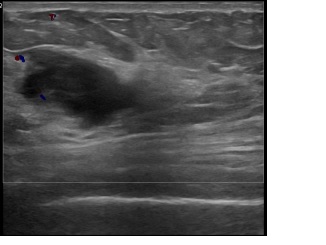

아산유외과개원후 832번째 유방암진단

상기환자는 좌측 겨드랑이 만져지는 멍울과 통증으로 내원하신 40대중반

여성분으로 의심스러운 좌측혹 조직검사 시행해 유방암으로 진단되었습니다